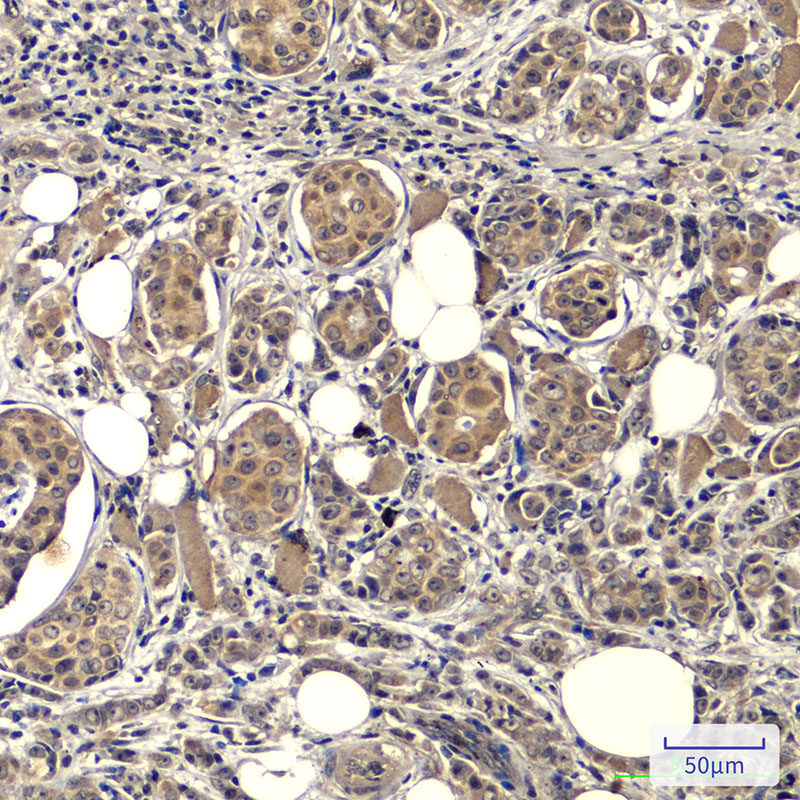

Mouse Monoclonal CytochromeC Antibody

中文名:Cytochrome C抗体

Catalog:IPDX20788

Size: 50μl / 100μl

Application: WB IF IHC ICC FCM Elisa

Reactivity:Human,Mouse,Rat,Chicken